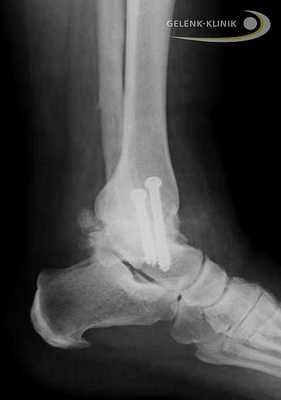

Рис. 1. Рентгенограммы пациента К. в опоре при поступлении: асептический некроз блока таранной кости, дефект малоберцовой кости, эквино-вальгусная деформация левой стопы

Рис. 2. Рентгенограммы пациента К. после операции: большеберцово-таранно-пяточный артродез с устранением всех видов деформации голеностопной области, фиксация проведена ретроградным блокируемым гвоздем Osteomed

После проведенного клинико-рентгенологического исследования пациенту был поставлен диагноз: Приобретенная посттравматическая деформация левого голеностопного сустава как следствие асептического некроза блока таранной кости. Несостоявшийся анкилоз левого голеностопного сустава. Не опорная левая стопа. Синдром крузалгии, тарзалгии слева (рис. 1).

Больному предложено хирургическое лечение, согласие пациента на хирургическое лечение получено. Выполнена операция: корригирующий большеберцово-таранно-пяточный артродез слева, фиксация ретроградным блокируемым гвоздем Osteomed, костная аутопластика (рис. 2).